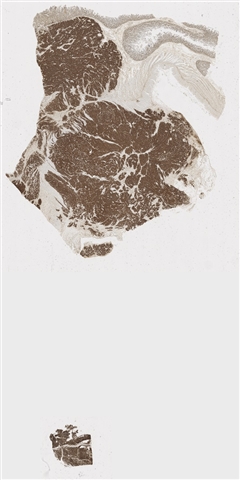

案例2 (6843)

患者详情: 因“反复便血一周“入院。患者1周前无明显诱因出现便血,为新鲜血液,大便为粘液血便,伴腹胀、头晕。外院肠镜:距肛门口4cm可见菜花样肿物,约3cm,宽基,组织脆弱易出血,表面糜烂,边界尚清,肠镜难以通过。病理提示:直肠恶性肿瘤,考虑为神经内分泌肿瘤。既往“高血压”10余年,其他无特殊。患者强烈要求局部切除。 临床诊断:直肠恶性肿瘤;高血压3级

取材部位: 直肠

大体所见: (直肠肿物)4 X 2.5 X 1.5cm灰黄肿物一个,表面粘膜粗糙增厚,切面灰黄灰红,肠壁结构观察欠清,实性质中,可见出血。

免疫组化: CK,CD56,CgA,Syn,SSTR2,Ki67

医院: 中山大学附属第三医院